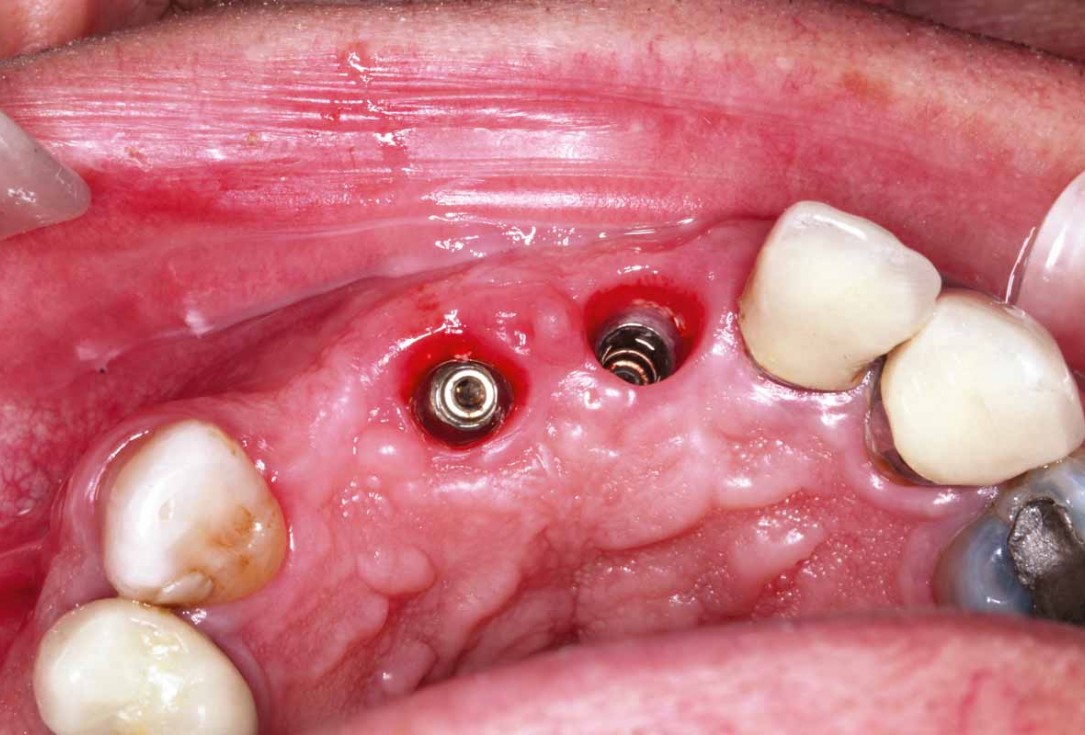

7/27 - Implants with healing capsGBR and soft tissue augmentation with cerabone® and mucoderm® - H. Maghaireh & V. Ivancheva

8/27 - Implants #11 and #21: occlusal viewGBR and soft tissue augmentation with cerabone® and mucoderm® - H. Maghaireh & V. Ivancheva